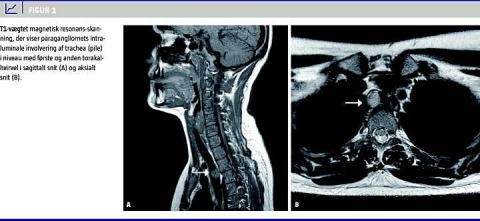

Patienten blev overflyttet til øre-, næse- og halsafdelingen med henblik på rigid bronkoskopi. Præ-operativ magnetisk resonans-skanning (MR-skanning) viste en 1,5 centimeter stor endotrakeal tumor, der var lokaliseret til højre på bagvæggen i niveau med jugulum (Figur 1 A og Figur 1B). Patienten, som nu var i 17. graviditetsuge, blev intuberet med tuben placeret lige under tumor. Tumor blev reseceret med optiktang og koagulationssug gennem et smalt laryngoskop (8590 DN-scope - Karl Storz).